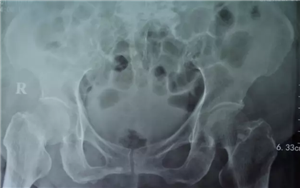

(术前)